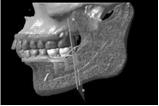

入れ歯を使っている人と使っていない人の顎の骨の厚みは違う

これは入れ歯を長年使い続けたことによって、歯を支える骨が溶けてしまっている患者さんのCTデータ三次元立体構築画像です(写真②)

こちらは通常の人の顎の骨です(写真①)

この写真を見てお分かりのように同世代の人でも入れ歯を使っている人と入れ歯を使っていない人では、

顎の骨の高さ厚みが違うのです。

顎の骨の高さ厚みが違うということは、つまり、

顔貌(かおかたち)も大きく違ってくるということです。

下顎の中に丸い穴(矢印のところ)が見えると思います。

これは下歯槽神経といって下顎の中で一番大きな神経が骨の外にでてくる穴(オトガイ孔)です。

通常は写真①の方のようにちょうど骨の高さの真ん中ぐらいに位置します。

次に写真②をご覧下さい。

本来骨の高さの中央部分にあるはずの穴が上に向いて開いています。

つまり大きな神経や血管はとても大切なので、本来骨の奥深くに埋まって保護されているのです。

しかし、骨が大幅に溶けてしまって大きな神経が歯茎直下にまで出てきてしまっているのです。

歯があるときから神経が上にでているということは考えられませんので入れ歯を何年も使っていたために

本来骨の中にある神経のところまで骨吸収が起こったと考えられます。

神経が骨よりも上に出ていて入れ歯でこすられる状態ですので、

入れ歯を入れただけでも飛び上がるほどの痛さです。

白黒の立体画像では骨の高さや厚みと、神経の出口、歯の形などが分かりますが、

神経がどんな走行をしているかはわかりません。

そこで、詳しく骨の中の状態を見るためにはCTデータ3D立体構築画像変換検査をしていきます。

この検査によって3次元的に対象部の形態や位置関係をさらに詳しく知ることができます。

これは骨が溶けて神経が露出している状態です

この検査によりどこに重要な神経が通っているか一目瞭然です。